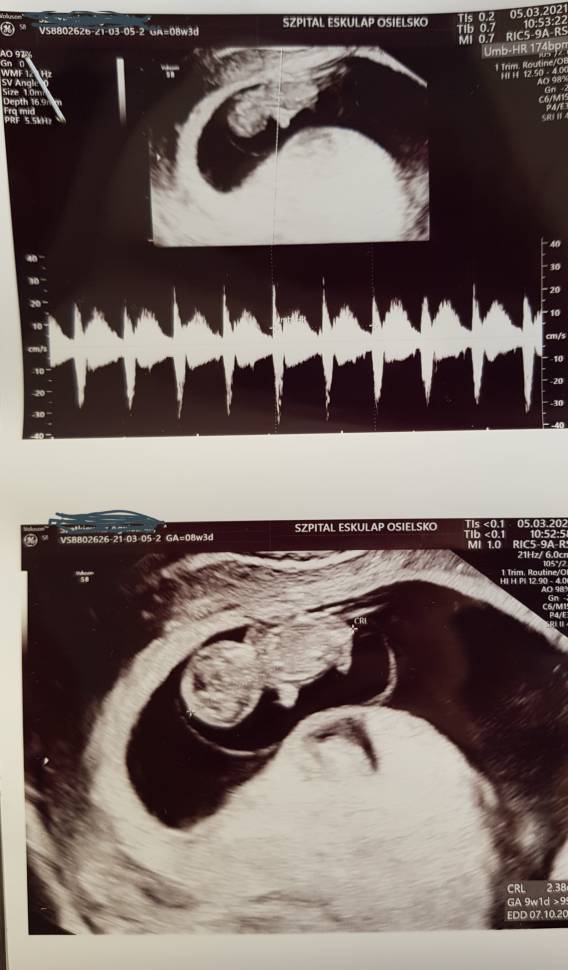

Rośniemy. Wyszliśmy z fazy krewetki i jest już faza człekokształtna [emoji6] Czuję się słabo ale wszystko zniosę. W moim przypadku działa zestaw Clexane 0.6, acard 150, encorton 10 mg, prolutex 25 mg zastrzyk, luteina 100 mg 3x2. Do tego witaminy i suple. Takie wysokie dawki progesteronu (profilaktyczne bo nie miałam stwierdzonych problemów) chyba nasilają nudności. Ale marzyłam o tym dziecku więc zaciskam zęby i czekam na przypływ mocy. Mi immunolog odradzał jakiekolwiek badania immuno przy jakiejkolwiek infekcji. Myślę że to by miało duży wpływ na cytokiny. Kazał w razie infekcji odroczyć o 2- 3 tygodnie. Szkoda kasy. Jeśli możesz to poczekaj z badaniem ten miesiąc. Zobacz załącznik 1245767